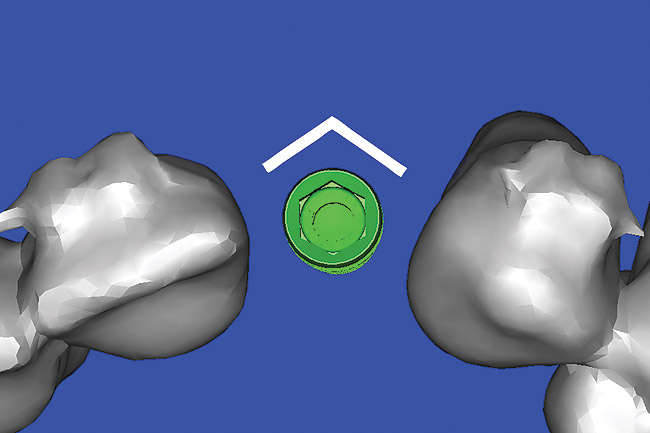

The CT axial views represent an important instrument in gaining a better understanding of anatomical features that cannot be determined by any other imaging modality (Figure 10). When the maxilla is sliced axially at the level where the roots meet the crest of the bone, the adjacent and surrounding root morphology can be revealed. Of note are the individual and different shapes of each of the central incisors, canines, premolars, and molar roots. These images reflect a phenomenon defined by the author as the “restorative dilemma.” Clinicians encounter this often difficult dilemma when attempting to re-establish morphologically correct emergence profiles in prosthetic teeth as they ascend from the round shape of the implant(s). When planning for the placement of the implant in the left lateral incisor area, there appeared to be adequate mesial-distal space between roots as seen in the axial view of Figure 11. A closer inspection of the planned site for the right lateral incisor revealed a more narrow space, further complicated by the distal rotation of the palatal aspect of the tooth root. Based on this preliminary position, the 3.75-mm diameter, straight-walled implant can be seen encroaching on the lamina dura periodontal ligament space of the right canine and central incisor. If there was not adequate room for this diameter and type of implant, the adjacent teeth could sustain potential iatrogenic damage. Therefore, additional “tweaking” of the virtual placement was necessary to diminish this risk.

Figure 10  SOFTWARE IMAGING By slicing the maxilla axially, the images revealed the differing morphology of the central incisors, canines, premolar, and molar roots.

Figure 10

Figure 11  SOFTWARE IMAGING  The left simulated implant can be seen encroaching on the adjacent lamina dura.

Figure 11